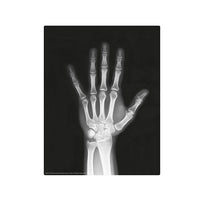

Build a full human skeleton set, complete as glow magnets. Learn how the skeleton supports our body. Includes “magic” x-ray films that let you “see through” the human body!